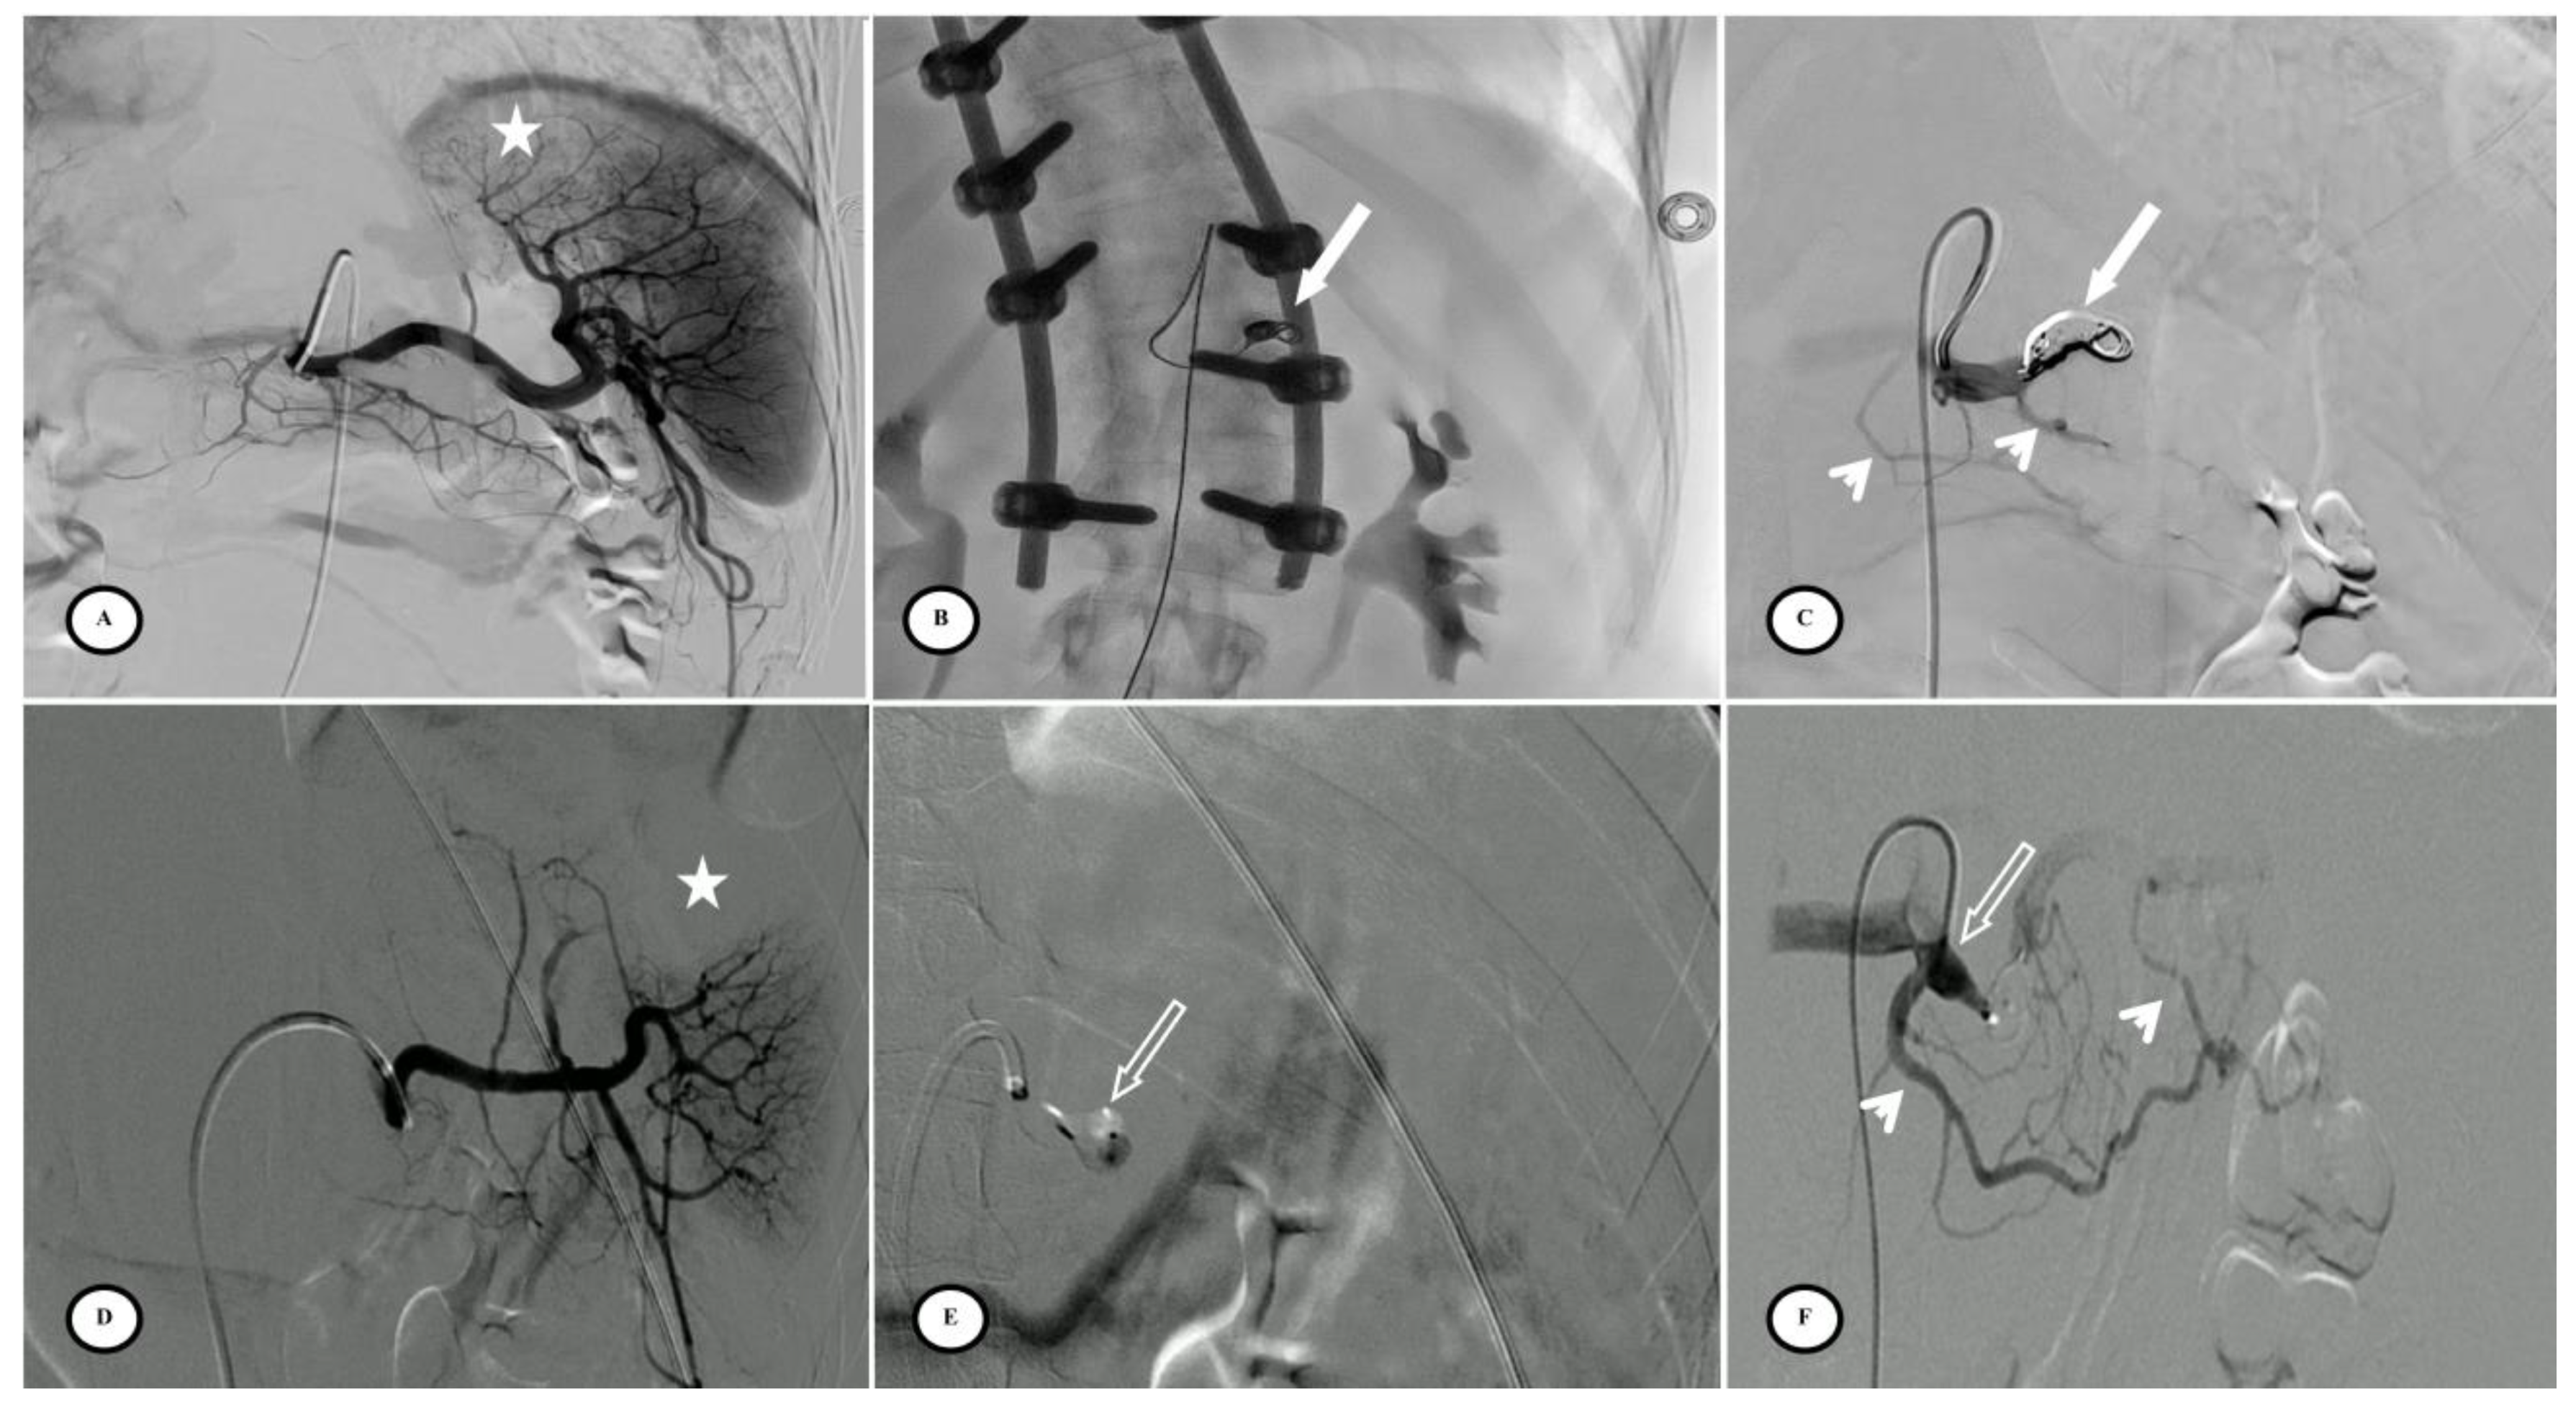

Figure 3.

Preventive proximal splenic artery embolization materials. (A) Upper pole splenic trauma without focal vascular anomaly (star). (B) Penumbra occlusion device (arrow) deployment through a microcatheter along the left lateral aspect of the spine; note that the patient had osteosynthesis material. (C) Final control shows complete flow stasis in the splenic artery downstream from the embolic material (arrow) and the development of collateral circulation (arrowheads). (D) Another upper pole splenic trauma without focal vascular anomaly (star). (E) Amplatzer vascular plug deployment (blank arrow) directly through the Cobra 2 4F catheter. (F) Final control displays the development of a collateral pathway through the dorsal pancreatic artery and the great pancreatic artery (arrowheads).

Technical success was achieved in 54 of the 57 patients (94.7%) with complete splenic artery stasis and the development of collateral circulation. Inadvertent distal coil migration occurred in four patients in the other coils group (n = 4/10, 40%; p < 0.01). There were no procedural complications with AVP or POD. The mean procedure time for all techniques was 56.5 min (SD = 38.1 min) with no significant difference between groups. The mean quantity of iodine contrast injected was 70.0 mL (SD = 42.0 mL), with less contrast injected in the AVP group (p < 0.01) (Table 3).